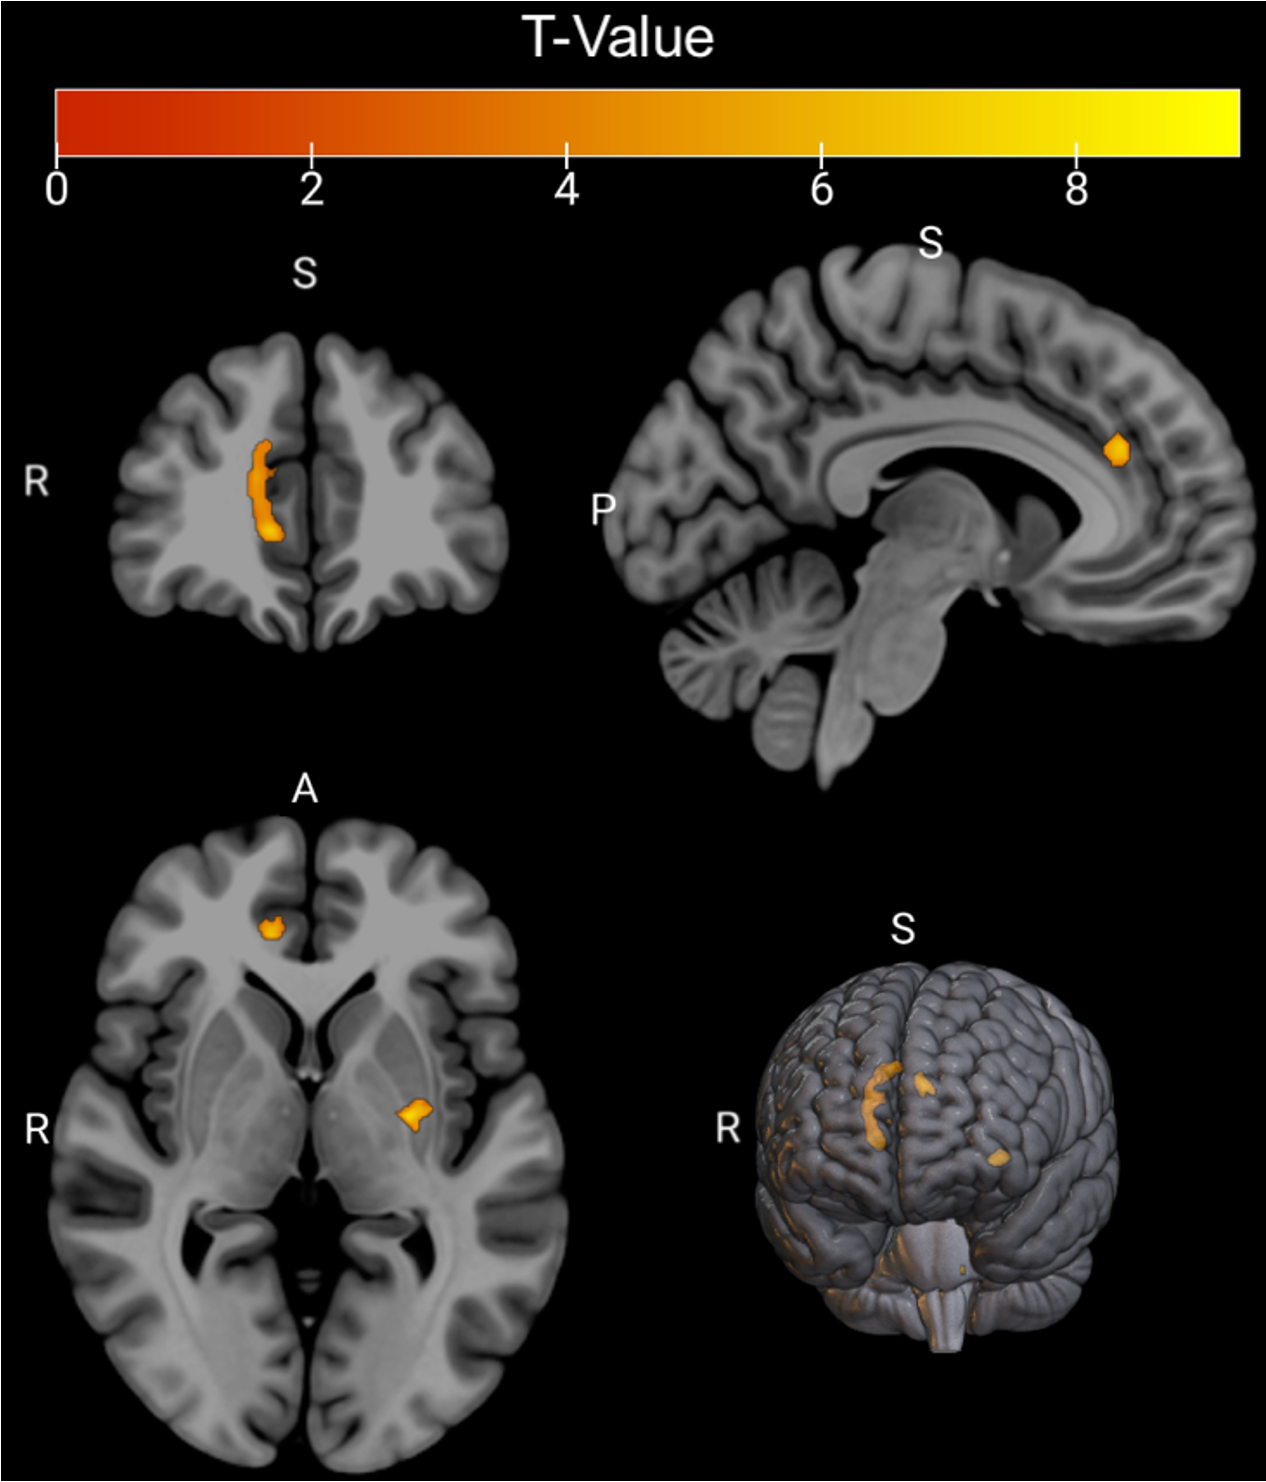

Background

This study explored whether Myelin Water Imaging could detect myelin injury in Anti-NMDA receptor autoimmune encephalitis (NMDAr-AIE), where traditional neuroimaging is often normal. Myelin Water Fraction (MWF) quantifies myelin content by distinguishing myelin sheath water from other brain water compartments.

Methods

Adult participants with confirmed NMDAr-AIE diagnoses and healthy controls (HC) underwent 3T brain MRI (Magnetic Resonance Imaging) including MWF mapping. Participants were recruited after discharge from the hospital. Mean MWF was calculated for 4 white matter regions of interest (ROI). MHI (Myelin heterogeneity Index) was calculated by dividing the MWF standard deviation by the mean MWF. Patient demographics, clinical assessments, treatment, and outcomes were collected.

Results

Five participants with NMDAr-AIE (4F/1M, mean age 30, SD 7) and four HC (3F/1M, mean age 36, SD 6) were included. All NMDAr-AIE participants had normal or non-specific T2 hyperintensities on initial imaging and had received immunotherapy. The mean Modified Rankin Score (MRS) on discharge was 2. MWF (mean ± SD) for normal-appearing white matter, corpus callosum, corticospinal tract, and superior longitudinal fasciculus were 0.10±0.02, 0.12±0.02, 0.15±0.03, 0.12±0.02, which were very similar to HC at 0.09±0.02, 0.11±0.01, 0.15±0.02, and 0.11±0.02, respectively.

Fig. 1 Myelin Water Imaging of two selected patients

Screenshot 2025 06 01 at 12.05.23 pm

Conclusions and Future Direction

Myelin Water Imaging showed no myelin pathology in five NMDAr-AIE patients, with MWF and MHI values comparable to HC, suggesting that myelin pathways are relatively preserved post-recovery from AIE. Moving forward, we aim to continue recruiting healthy controls, patients post-recovery and those experiencing active disease to determine if there are any MWF abnormalities throughout the disease course. Future studies are needed to assess MWF changes in other antibody-mediated encephalitides.